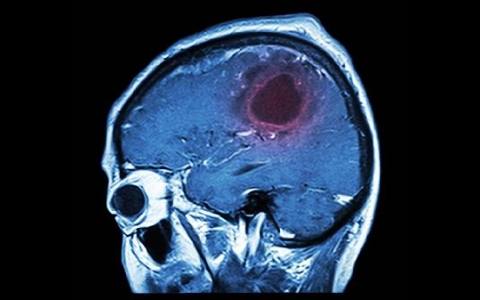

面对脑瘤手术成功率你了解多少?

不久前我接诊了一位中年男性患者,他因为头痛、恶心、呕吐等症状来到医院就诊,经过CT和MRI检查,确诊为脑瘤。我建议这位患者做手术治疗,他的家属非常担心手术的成功